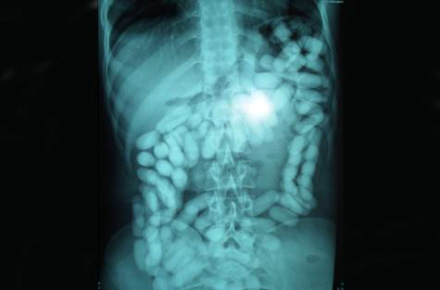

I alt er 21 narkosmuglere fanget i år med kokain eller heroin i mavesæk eller endetarm i Københavns Lufthavn. Det er syv gange så mange som sidste år, hvor tolderne kun fangede tre smuglere med narko i kroppen, viser nye tal fra Københavns Politi. Derudover blev blandt andet en mandlig smugler anholdt i Billund Lufthavn i juli måned efter at have smuglet et kilo kokain i maven fra Spanien.

De sluger fra 500 gram og op til et kilo narko, mens én mand er taget med hele 1,233 kilo narko i organerne. Typisk smugles kokain, men også heroin finder vej til danske misbrugere i smuglernes maver.

Det er tydeligt at se poserne med narko på scanningsbilleder